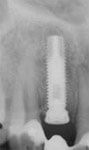

Röntgenbild mit Schraubimplantat

Das Röntgenbild mit dem Implantat und der provisorischen Klebebrücke.